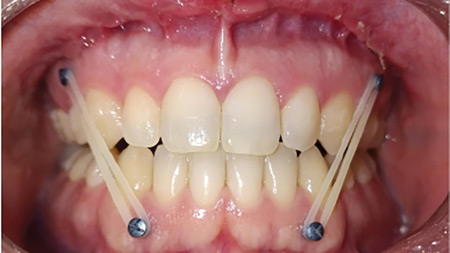

Orthognathic Surgery with Clear Aligner Therapy

The rise of the digital age has transformed orthodontics as we know it.1 Due to its increasing popularity, Clear Aligner Therapy (CAT) has become a mainstay of contemporary orthodontics.2 This trend is largely due to the growing demand among prospective patients for more esthetic alternatives to traditional brackets and wires, including those presenting with dentofacial … Read more